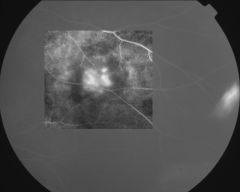

IM000030